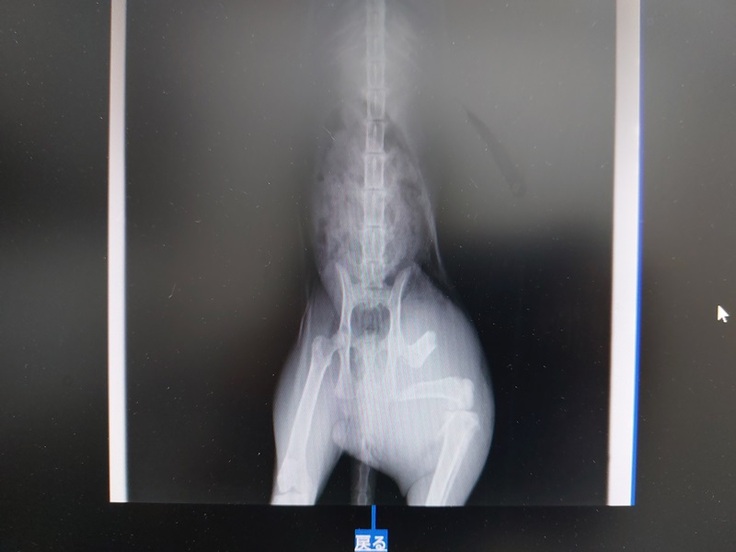

すぐに一次診療の動物病院で診察を受け、レントゲン検査を行いました。

診断の結果、大腿骨の骨折が判明。

しかし、骨折は今回の事故によるものではなく、以前からのものだということがわかりました。それでも体は衰弱しており、しばらくの間、京都どうぶつあいごの会で預かることになりました。